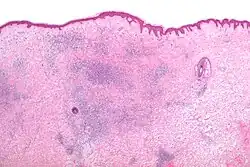

Микроскопия

Гистоморфологические появления укусов насекомых, как правило, характеризуются появлением сосудистого инфильтрата, состоящего из лимфоцитов и эозинофилов.